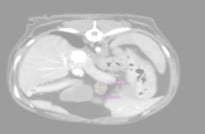

시그니처동물의료센터 『동물 종양 센터』에서는 림프종(lymphoma)과 같은 혈액암, 비만세포종(Mast cell tumor)을 비롯한 피부암부터 인슐린종(insulinoma)와 같은 희귀 내분비종까지 경험 많은 종양 의료진들이 각 환자에게 정확한 진단 및 적절한 치료를 이어나갈 수 있도록 노력하고 있습니다. 최소한의 마취로 CT 촬영을 통한 전이 평가, 외과적 절제술, 항암 치료까지 각 환자의 상태에 따라 최선의 치료를 이어갈 수 있도록 내외과 및 영상의학과의 의료진들이 협진하고 있습니다.